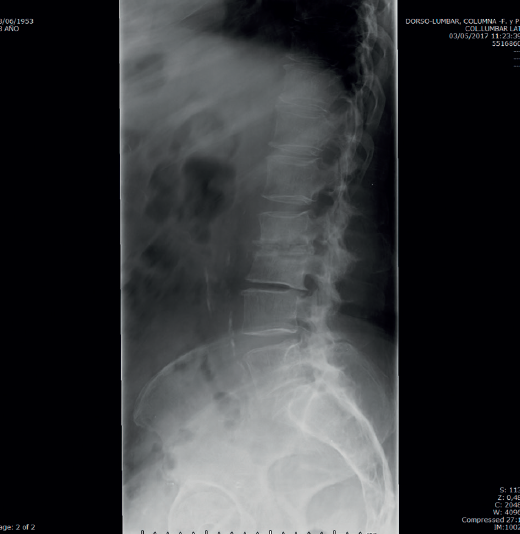

• Resonancia magnética (RM) lumbar (Figura 2): sagitales con secuencias T2 y STIR. Espondilodiscitis aguda con absceso en canal raquídeo y prevertebral.

Figura 2. Resonancia magnética sagital T2 y STIR.